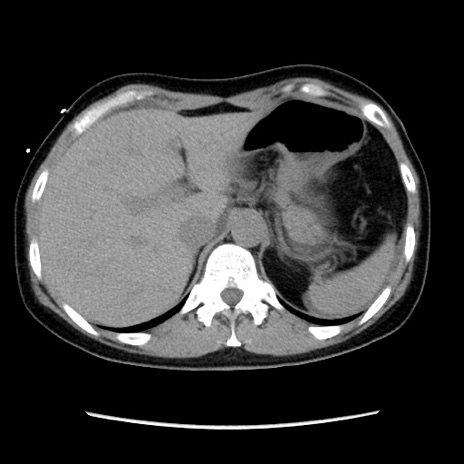

症例10(横断像)

【症例】 50歳代女性

【主訴】 腹痛

【現病歴】前日生レバーを食べた。今朝に排便あり。 昼前に突然発症の腹痛を生じ、当院救急外来を受診した。

【既往歴】 子宮筋腫にてで子宮全摘後

【身体所見】 意識清明、腹部:平坦、軟、下腹部やや左を中心に圧痛・反跳痛あり、筋性防御あり

【データ】WBC 7800、CRP 0.07